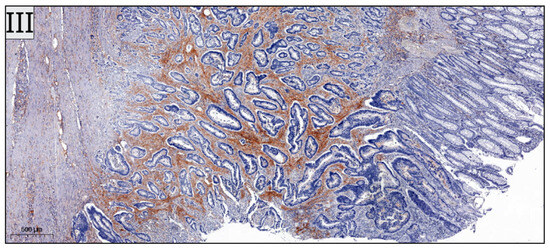

B and T Tumor-Infiltrating Lymphocyte Subtypes According to Subsite: A Colon Cancer Immunophenotyping Map

by Giorgiana Fagarasan, Bogdan Alexandru Gheban, Vlad Fagarasan, Doinita Crisan, Teodora Telecan, Vasile Virgil Bintintan, Radu Ioan Seicean, Alexandra Caziuc and George Calin Dindelegan

Background: Accumulating evidence regarding the association between tumor-infiltrating lymphocyte (TIL) subtypes and prognosis in colorectal cancer has emerged recently in the literature. Whether the prognostic impact of TIL subsets is different according to tumor location remains unknown, despite genetic, epigenetic and molecular differences [...] Read more.

Background: Accumulating evidence regarding the association between tumor-infiltrating lymphocyte (TIL) subtypes and prognosis in colorectal cancer has emerged recently in the literature. Whether the prognostic impact of TIL subsets is different according to tumor location remains unknown, despite genetic, epigenetic and molecular differences between the proximal and distal colon. Our study aimed to investigate the value of CD3+ lymphocytes, reflecting overall T-cell infiltration, CD8+ cells identifying cytotoxic effector T-cells and CD73+ cells acting as a modulator of immunosuppression, stratified by primary tumor location. Methods: The density of CD73+, CD3+ and CD8+ tumor-infiltrating B- and T-cells was determined in colon cancer patients using whole-section tissue sampling, heat-induced epitope retrieval, primary antibodies and DAB visualization. QuPath Cell counter function quantified nucleated cells and immune-positive percentages; ImageJ assessed staining intensity via color deconvolution and optical density. An Immunoreactive Score combined intensity and positivity for immune profiling. The Receiver Operating Characteristic (ROC) curve analysis was used to determine the optimal cut-off values for CD3+, CD8+ and CD73+ lymphocytes. Statistical analysis was performed in order to identify potential associations between TILs expression and pathological characteristics, according to the location of the primary tumor. Survival analysis was carried out using the Kaplan–Meier method. Results: A total of 100 patients were included in the study. CD3+ T-cells were the most abundantly expressed and were more predominantly encountered in the right colon. Total CD3+ numbers were correlated with T stage and the presence of perineural invasion in left-sided tumors, as well as with tumor grading in the right colon. Correlation analysis based on CD3+ threshold values according to tumor location demonstrated a statistically significant association between a higher N stage and low CD3+ cell values (p value = 0.0306), and higher perineural invasion and low CD3+ TILs values in the left colon (p value = 0.0123). In addition, low CD8+ values were associated with a higher T stage in the left colon (p value = 0.0382). Survival analysis did not demonstrate statistically significant differences between the investigated groups. Conclusions: TIL subtypes in colon cancer patients demonstrate significant variability according to the location of the primary tumor and are associated with different clinical and pathological characteristics. This exploratory study requires larger validation before TIL densities can guide therapy. Full article